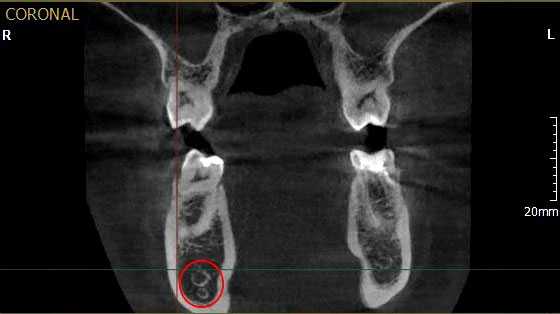

Рис. 1. Асимметричное строение нижнеальвеолярного нерва, добавочный канал в области нижней челюсти справа во фронтальной проекции конусно-лучевой компьютерной томографии от Vatech.

Результаты рентгенологического исследования показали, что дентальная объемная томография наиболее информативный метод при оценке степени повреждения нижнего альвеолярного нерва. Истинное трехмерное изображение исследуемого объекта и вращение его вокруг любой из трех осей на 360 градусов, позволяют визуализировались положение имплантата по отношению к нижнечелюстному каналу и документировать степень его повреждения. Программное обеспечение Ez3D-iV4.3.0 от Vatech предполагает огромный функциональный набор. Применительно к диагностике повреждения нерва после имплантации в данном софте в режиме высокого качества разрешения возможна трехпроекционная реконструкция, с возможностями переориентации осей, с измерением габаритов объекта исследования в масштабе 1:1(рис.3).

Рис.3 Конусно-лучевая компьютерная томография от Vatech. На коронарной проекции определяется верхушка дентального имплантата 3.6, перфорирующая медиальную стенку нижнечелюстного канала.